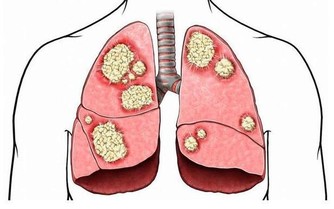

肺是人體極其重要的呼吸器官,是體內氧氣循環的關鍵。不過,現代很多人存在不良的生活和飲食習慣,比方說,時不時抽煙喝酒,動不動就熬夜……導致肺部功能或多或少受損,影響身體健康。那麼,肺好不好,可以通過哪些方法判斷?冬季養肺應該怎麼做?

肺好不好,不妨看看5個地方

不少存在嚴重肺部疾病的人,會出現杵狀指的情況,較為常見的就是手指頭增生粗大。

因此,想判斷肺部功能好不好,也可多觀察手指。若是手指粗細均勻,沒有指頭粗大現象,就說明肺部功能良好;而若是已經出現杵狀指,就可能是肺部病變了,建議及時就醫。